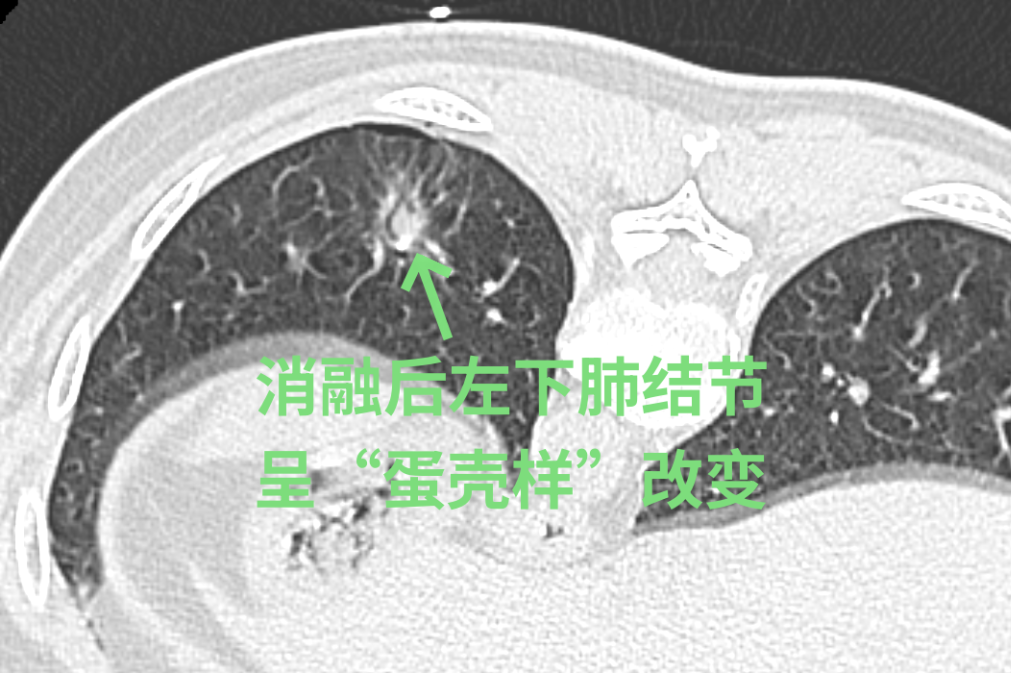

经过徐驯宇主任医师、黄郴副主任医师和王捷阳医师的反复讨论,决定为刘女士实施杂交手术:首先由黄郴和王捷阳在CT引导下为刘女士左上肺的小结节打上金属钩作为标记,然后再对左下肺较深的结节进行热消融治疗;接着由徐驯宇主刀为刘女士进行胸腔镜下左上肺结节的切除。在术中,徐驯宇按照之前在CT引导下置入的金属钩,很快就定位到左上肺的磨玻璃结节,并进行精准的局部切除,整个过程仅耗时30分钟。术后的病理报告显示,这3个结节分别为两个原位癌和一个非典型腺瘤样增生。经过量身定制的杂交手术,刘女士顺利解除了肺部的3个健康隐患,3天就顺利恢复出院。

▲术中结节变化